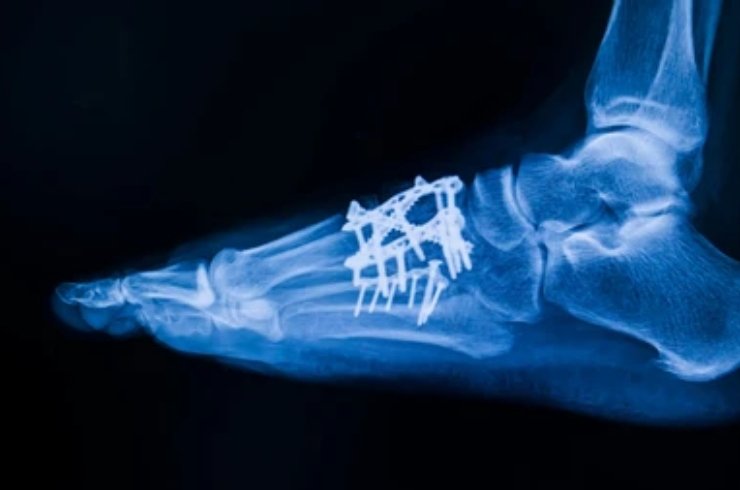

Orthopaedic